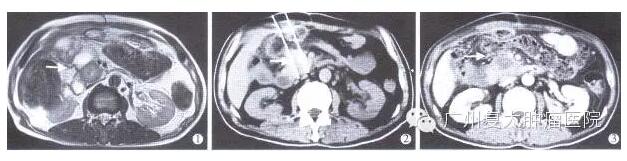

图为胰头部肿瘤IRE消融术前术后影像学改变

①术前MR显示肿瘤邻近十二指肠受压,肿块包绕邻近胆总管、胰管,肿瘤的大小为2.8cmX2.3cm;

②术中CT显示肿瘤中心插入主电极及标准电极各一支,电极距离为2.0cm;③术后30天CT增强扫描显示病灶中心无强化,范围较前略缩小